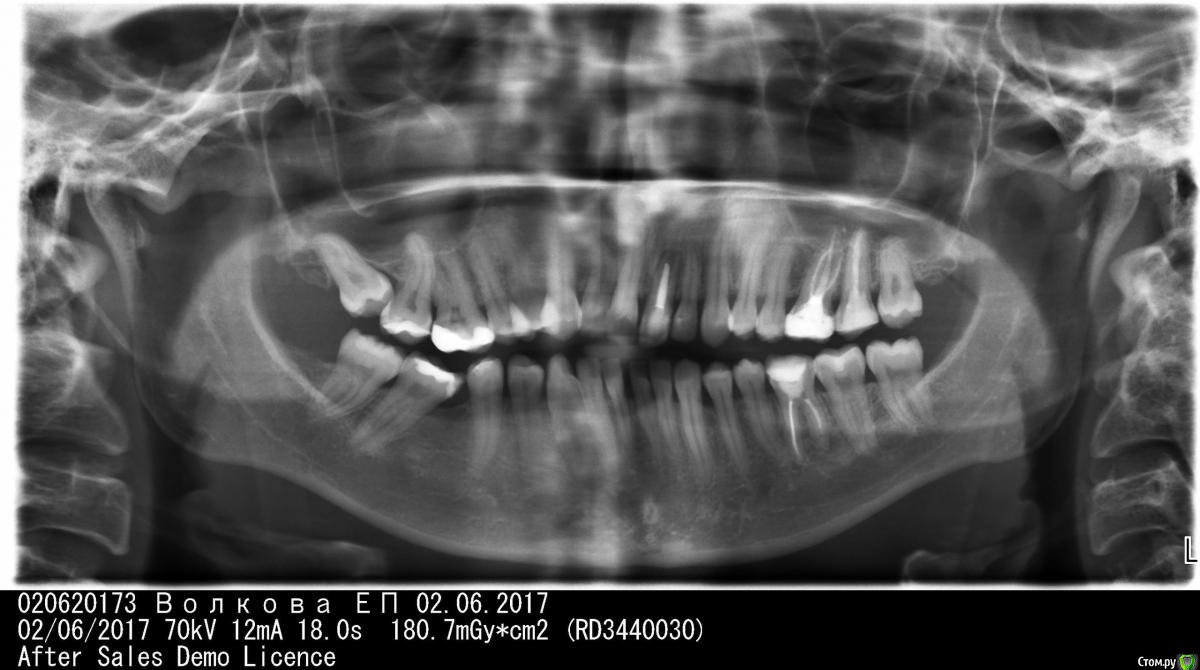

Елена 89 Опубликовано 8 июня, 2017 Поделиться Опубликовано 8 июня, 2017 Здравствуйте, Дорогие доктора! Помогите пожалуйста с диагнозом и лечением в следующей ситуации:Мне 27 лет, женщина.В детстве (пример лет в 12) у меня была травма переднего зуба, он начал качаться... мне его "гипсовали" не знаю как правильно называется. В общем он шатался, потом походила с "загипсованным" и он прирос. Но в следствии травмы, как мне уже сейчас сказали, корень не сформировался окончательно. Тогда меня это не беспокоило.Сейчас же я обратилась ко врачу со следующей картиной:У корня этого самого зуба на десне образовалась шишка (или прыщик) размером меньше 1 см, из которого иногда сочится гной. Он не болит, но иногда ощущаются пульсирующие неприятные ощущения, при надавливании чувствуется и сам зуб темнее соседних.Сначала мне поставили диагноз - киста, и предупредили, что надо добиться того, чтоб корень все же закрылся.Провели лечение:1) Почистили канал (зуб был мертвым)2) Положили лекарство (каласепт вроде) поставили временную пломбууже через пару дней прыщик (свищ) рассосался, зуб побелелЯ проходила так 2 недели3) Мне запломбировали этот канал Но уже через пару месяцев и прыщик вернулся и зуб снова потемнел и так мне делали 2 раза.Показывала этот же зуб другому врачу (при проф гигиене полости рта, тоже сказал киста)Предложил сделать операцию - разрезать десну и положить лекарство прямо туда (не через канал, а через десну). Или сделать резекцию корня.Мне показалось это хорошей идеей но я решила посоветоваться с первым врачем.Он же сказал, что у меня не киста, а разряжение костной ткани и это не очень лечится. Скажите пожалуйста что мне делать, зуб очень не хочется удалять (на снимке он передний запломбированный)Заранее Спасибо за помощь Ссылка на комментарий

Елена 89 Опубликовано 8 июня, 2017 Автор Поделиться Опубликовано 8 июня, 2017 снимок Ссылка на комментарий